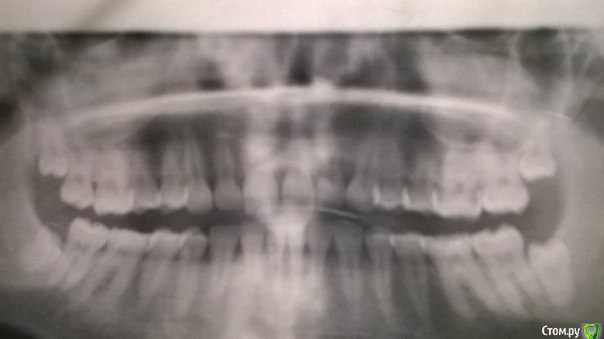

Bier Опубликовано 23 июня, 2016 Поделиться Опубликовано 23 июня, 2016 Панорамный снимок очень низкого качества, удалить зубы можно без проблем, ничего страшного не случится. Про "кисту" надо кт смотреть Ссылка на комментарий